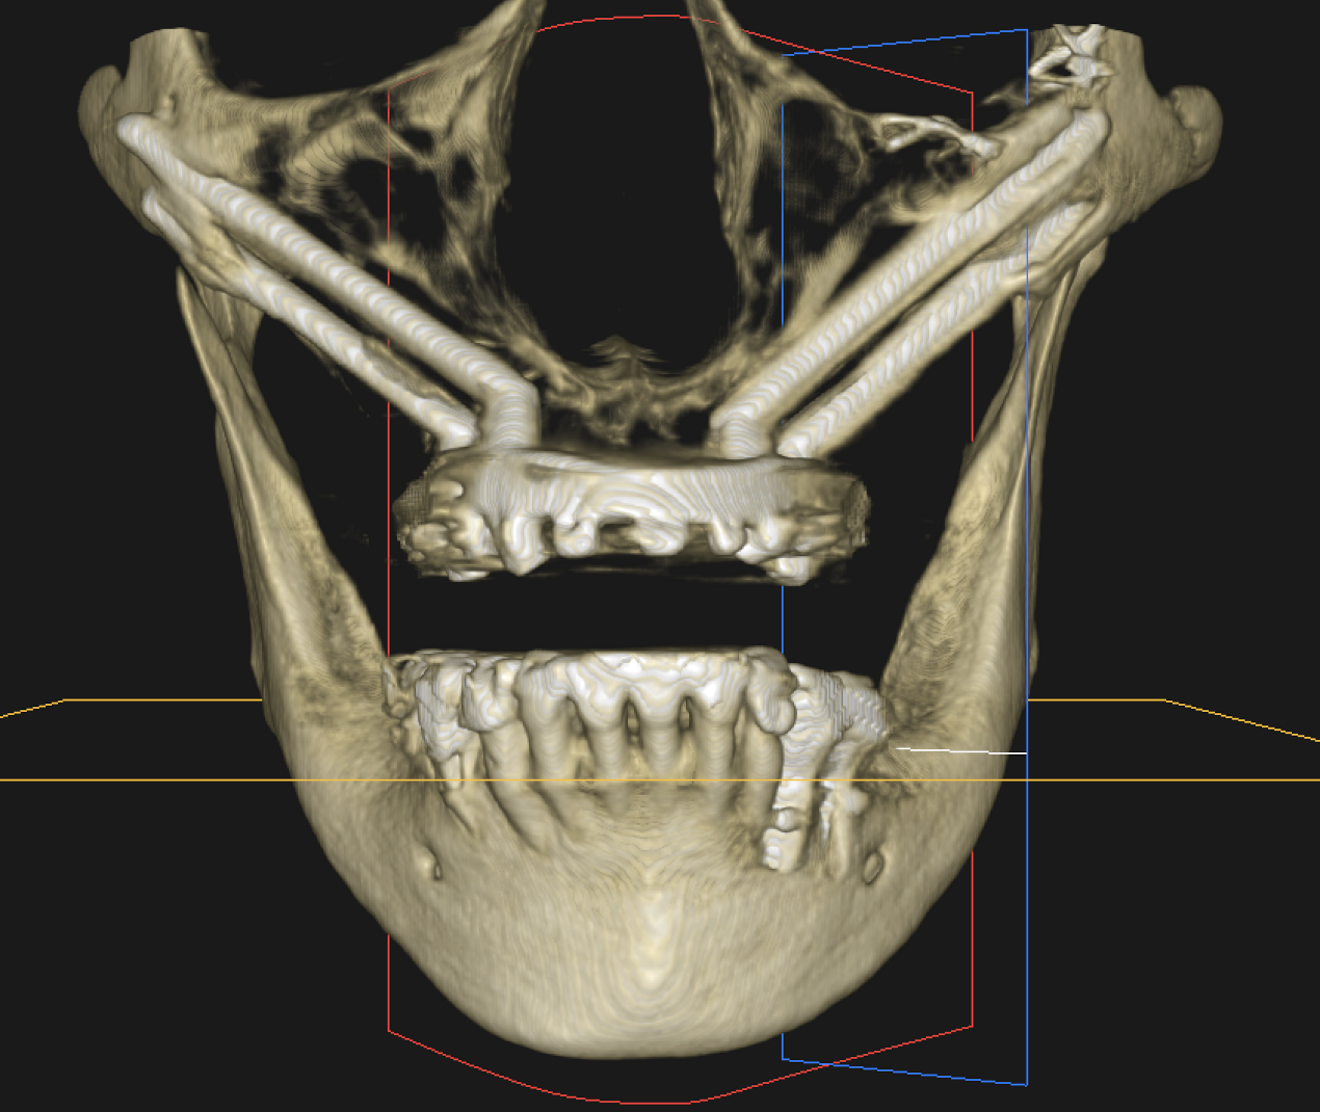

Fig. 2a : Photographie endobuccale d’ISP maxillaire.